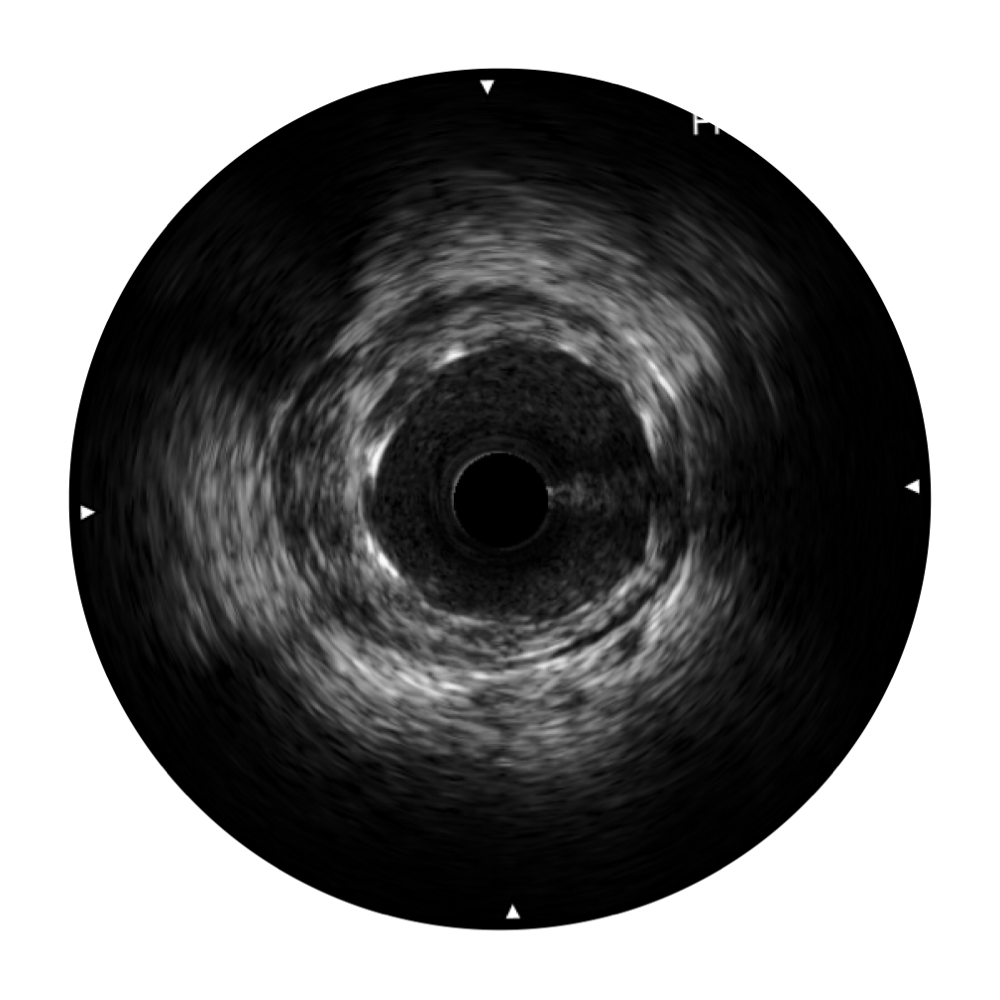

血管内超声(IVUS) 通过对病变程度、性质和累及范围的精确判断,可帮助选择治疗策略和方法,指导介入治疗过程,能够降低主要不良心血管事件,改善预后,在复杂病变介入治疗中用于指导支架置入的优势更为明显。血管内超声(IVUS)已成为精准心血管介入治疗的“金标准”。

云顶集团官网始终关注未满足的临床需求:超宽频成像技术同时提供高清分辨力和充足穿透深度,适应不同血管结构的治疗引导;智慧赋能,简化操作,降低临床应用难度和缩短学习曲线。